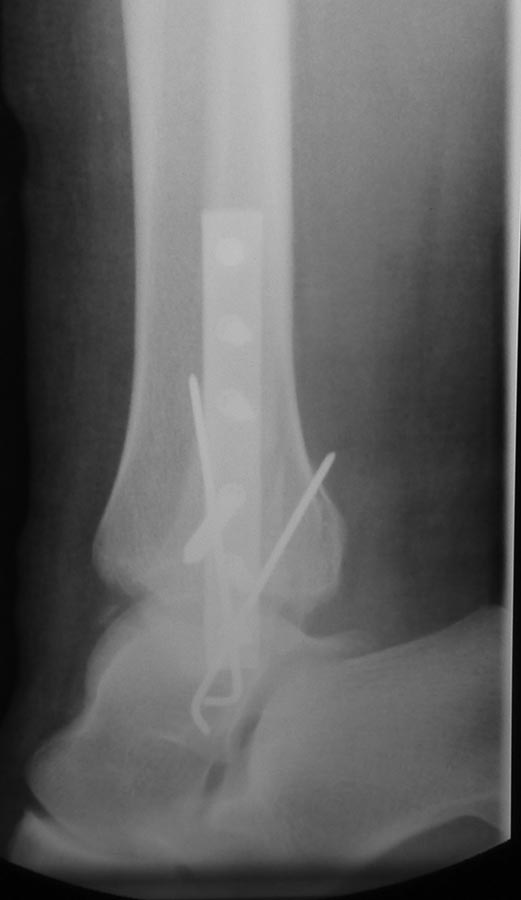

Отправлял до- и послеоперационные снимки, но почему-то проявились только послеоперационные. Досылаю остальные.

Основной диагноз: закрытый перелом лодыжек левой голени со смещением отломков, разрыв дистального межберцового синдесмоза, отрыв фрагмента переднего края левой большеберцовой кости, перелом заднего края левой большеберцовой кости без смещения отломков.

Сопутствующий диагноз: контрактура трехглавых мышц обеих голеней.

Я поддержу Максима. Не нравиться мне остеосинтез! Имплант модный, современный, репозиция наружной лодыжки идеальная, суставная щель какаду-то равномерная.....Какбуд-то.

Про репозицию: Медиальная лодыжка чуть не дорепонированв, реально медиальное щель уже, чем в норме. Про синдсмоз по этим проекциям судить нельзя. Сделайте КТ - можете удивиться тому, что найдете.

Про остеосинтез: перелом наружной лодыжки простой, отремонтирован идеально, а где стягивающий винт? Межберцовый винт: в его качестве locking had screw, а не обычный кортикальный? В каких руководствах или статьях есть такая рекомендация? Этот винт проведен через сам синдесмоз на 1 см проксимальнее сустава - а это в соответствии с какими рекомендациями? Вроде рекомендуют повыше немного?